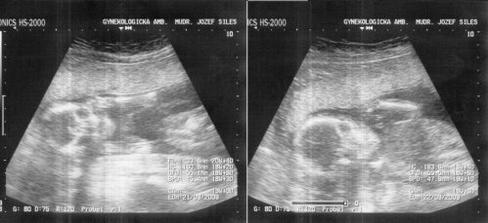

Naše twins 🙂 výbavička